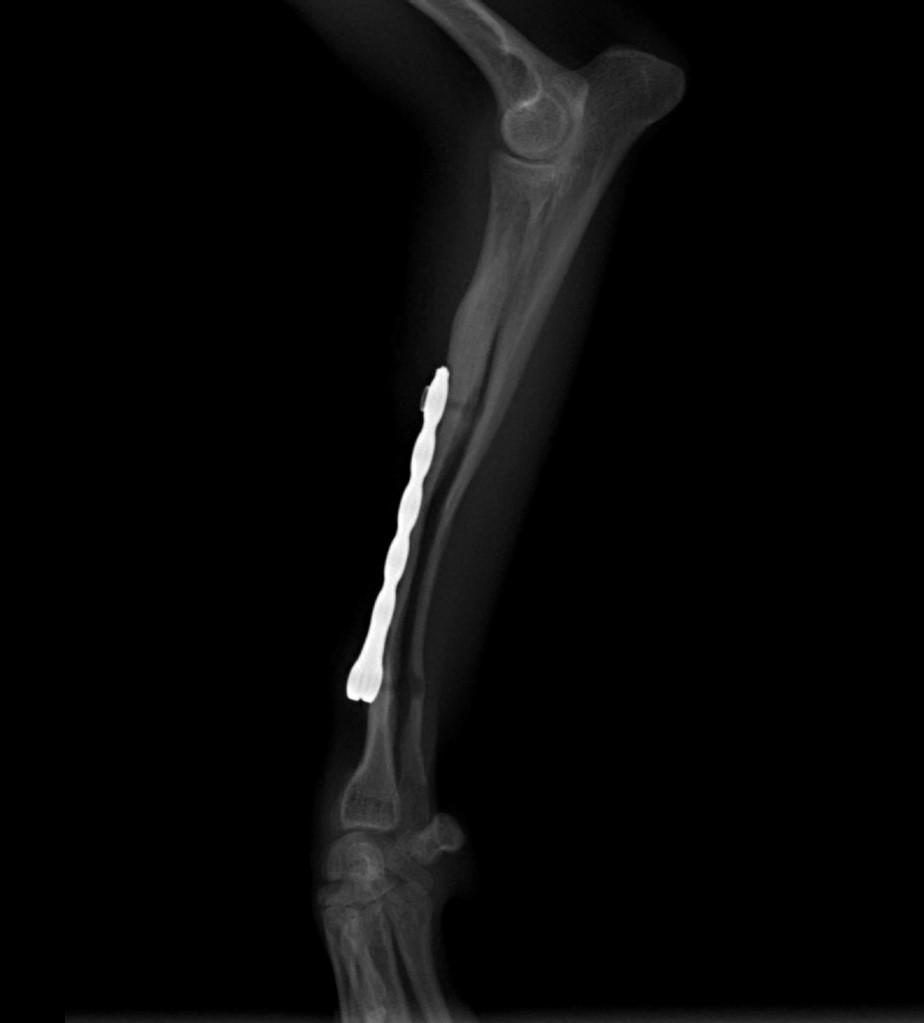

Radioulnar fracture in toy breed

Female, 5 months old, 1.7 kg Pomeranian dog

Right forelimb radiographs reveal complete closed distal diaphysis short oblique traumatic radial fracture with moderate cranial displacement, and distal diaphyseal transverse ulnar fracture minimally displaced.

A Fixin Micro-Series 1.7mm T-shape Cuttable Locking plate was used, with 3 screws on each bone segment.

Follow-up at 10 weeks post-op present good bone healing and a dynamization is performed, by removing 3 screws.